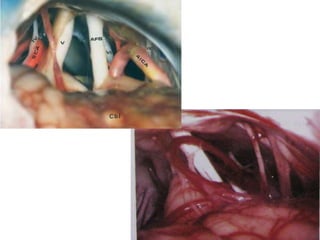

Accessories

anterior ethmoidal artery ( AEA) and nerve

(AEN) , anterior falcine artery (AFA)

Deep temporal artery